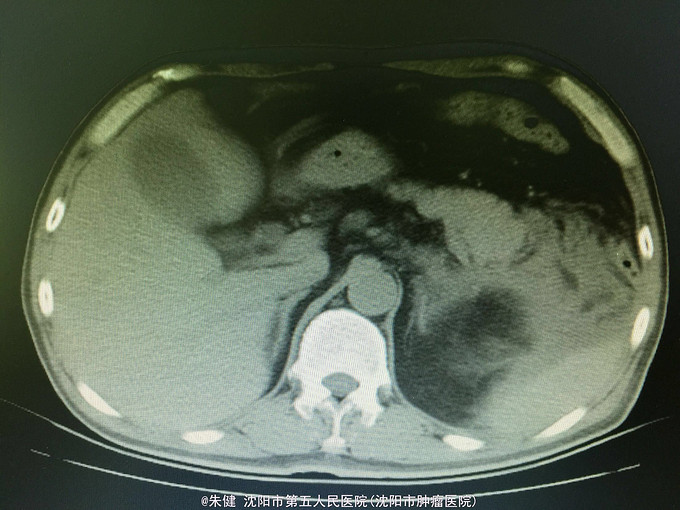

男,52岁 主诉:上腹部胀痛30小时, 现病史:30小时前饮酒后引起上腹部胀痛,持续性,逐渐加重,累及腰背部,恶心,呕吐数次胃内食物,无发热,未治疗,因不见好转来诊;病来无心悸、气短,排气、排便可,排尿正常。

一般状态可,腹部平坦,未见肠形及蠕动波,剑突下及左侧上腹部压痛,轻度肌紧张,未及包块,无移动性浊音,肠音正常,肾区无扣痛。 辅助检查:血常规:白细胞13.6*10^9/L,中性83.3/L;尿淀粉酶:214U/L,上腹部CT:左侧胸腔积液,左肺下叶可见斑片及索条状影;胆囊增大,胆道内未及结石影;胰腺形态及密度正常,胰腺尾部周围可见索条状影及积液影。

诊断:急性胰腺炎 处理:给予禁食、补液、抗炎及抑肽酶治疗,病情逐渐好转,一周后出院。